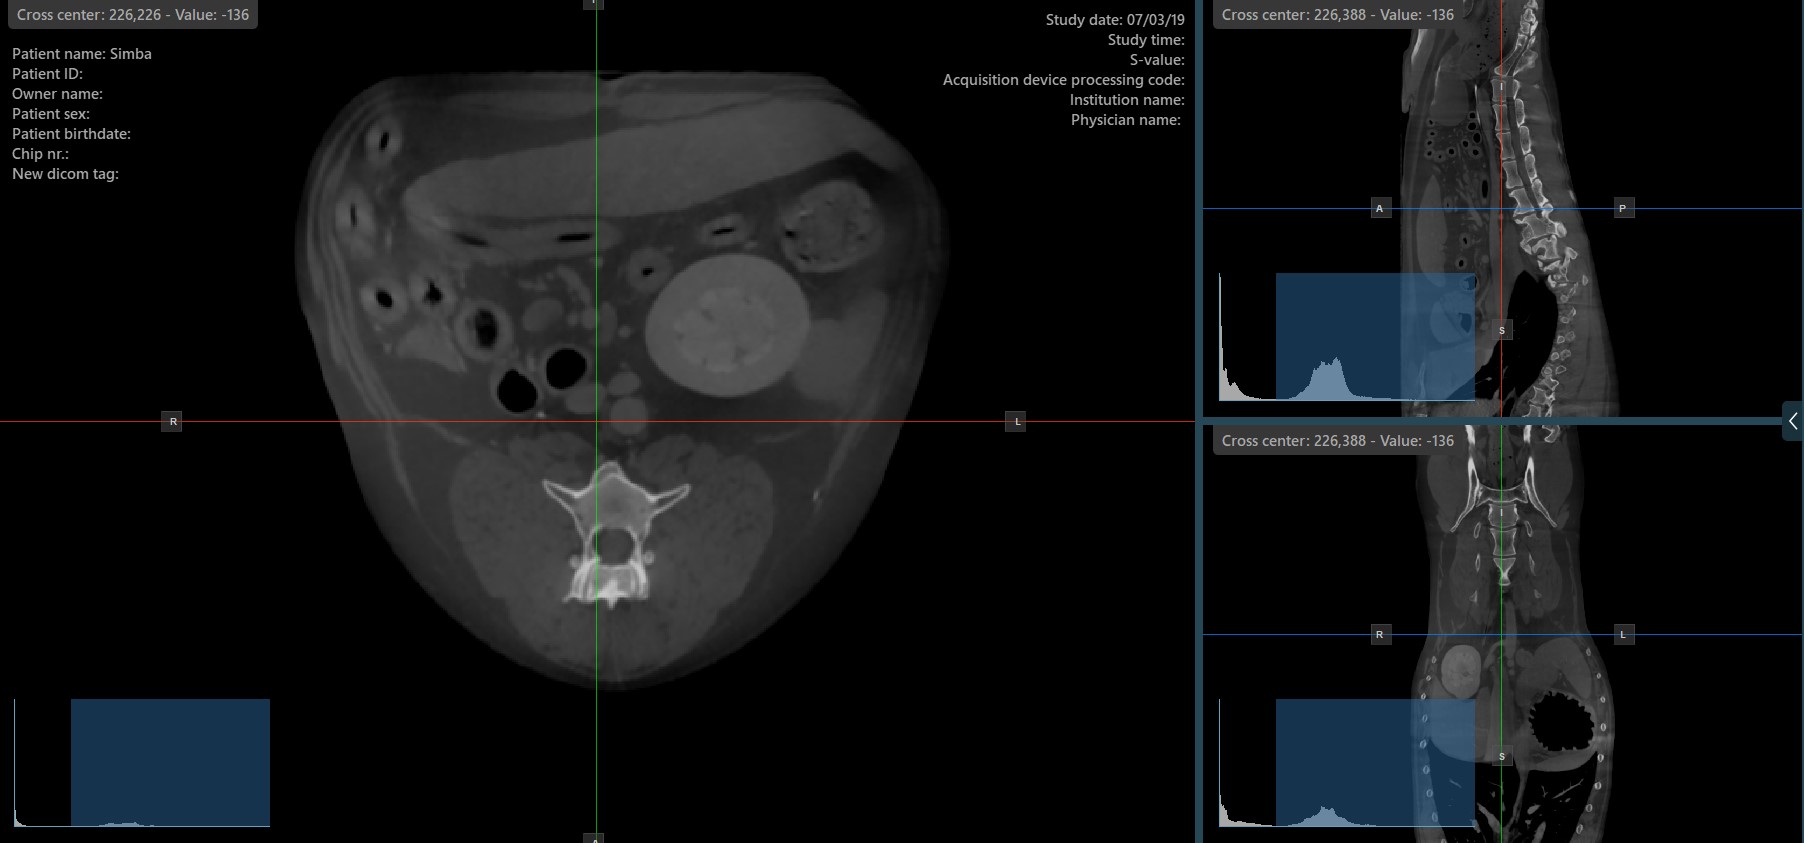

A szeletelők keresztközéppontjának módosítása¶

A szeletelők keresztközéppontjának módosítása megváltoztatja a megfelelő két kép síkjának helyzetét. A szeletelők keresztközéppontja a Elem kijelölése (Alapértelmezett) eszközzel választható ki, amely alapértelmezés szerint a jobb egérgombhoz van rendelve.

Miután kiválasztotta, húzza a szeletelők keresztközéppontját a kívánt irányba a pozíció módosításához.